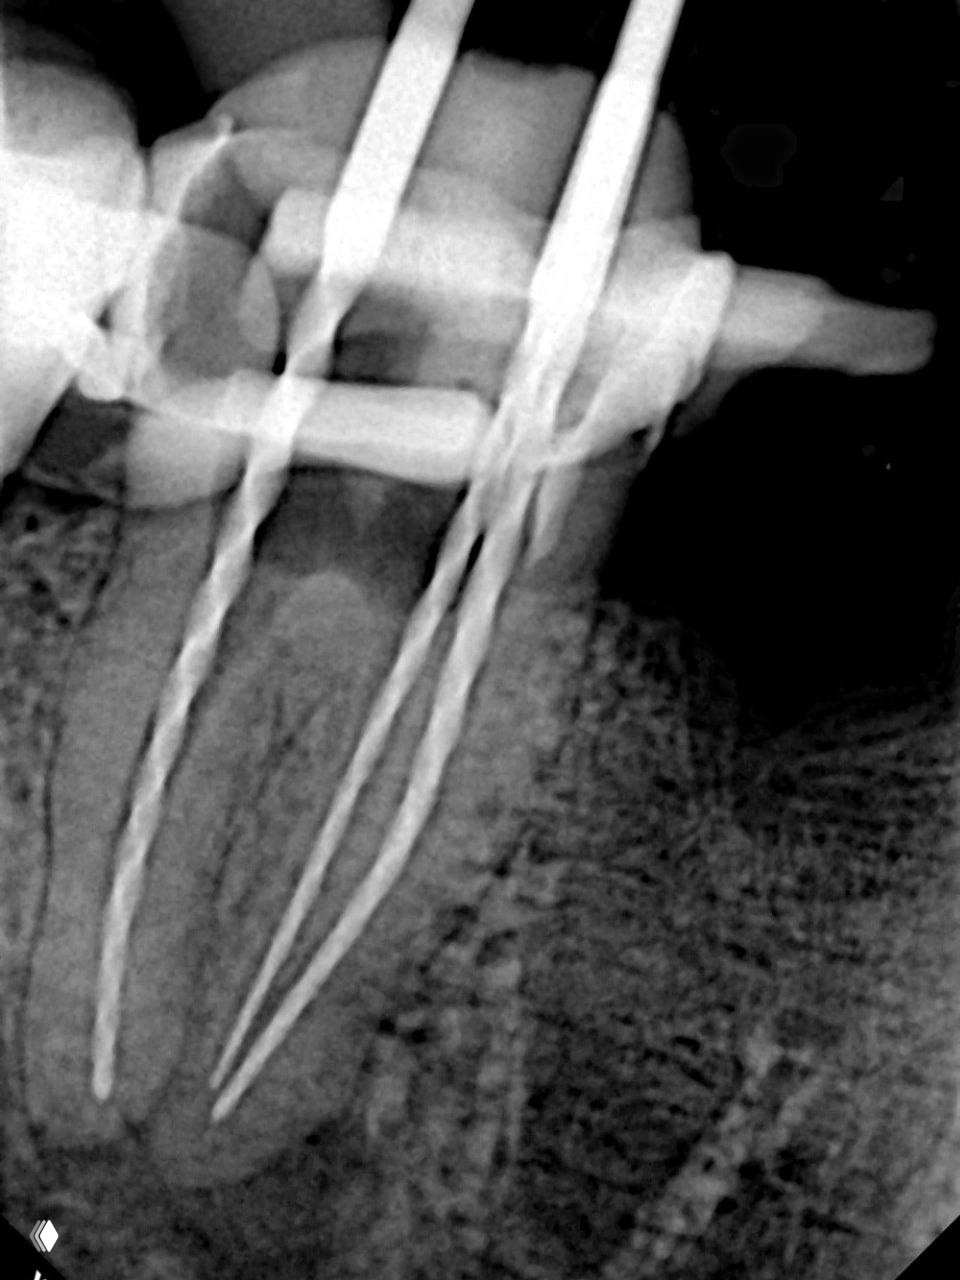

- 🔹 В первое посещение мы провели полную деобтурацию канала. Старый МТА аккуратно убрали с помощью эндочака и У-файла, который выпиливает материал и позволяет безопасно его извлечь.

- 🔹 Во второе посещение работа шла по чёткому плану. Сначала закрыли перфорацию быстротвердеющим Рутдентом. После этого дистальный канал обтурировали по методике Шилдера, а мезиальные каналы запломбировали методом вертикальной компакции непрерывной волной.